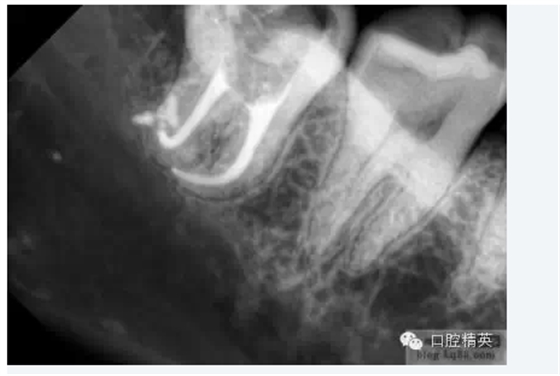

3.根管擴(kuò)大器械可以很明確的告訴我們整個(gè)根管系統(tǒng)的解剖情況。臨床牙醫(yī)需要對(duì)整個(gè)根管系統(tǒng)都非常熟悉,包括其根管的彎曲、分叉、融合等等。此時(shí)根管擴(kuò)大器械的根管探測作用即可派上大大的用場。它可以為我們提供非常詳細(xì)的資料:包括根管彎曲的部位及程度、根分叉的位置及分支多少。在應(yīng)用機(jī)用擴(kuò)大針之前,牙醫(yī)必須了解根管的解剖情況:究竟是在髓腔部位只有一個(gè)而在下方分為兩個(gè)甚至更多,還是在髓腔部位是幾個(gè)而在下方發(fā)生融合甚至有時(shí)情況更加復(fù)雜:如從髓腔部分向下依次為幾個(gè)根管向下融合為一個(gè)然后又發(fā)生分叉現(xiàn)象等。只有對(duì)整個(gè)根管系統(tǒng)的解剖結(jié)構(gòu)有了非常清楚的了解,并能確定已達(dá)到應(yīng)用機(jī)用擴(kuò)大針的條件,才有了成功的根管治療的基本保證。

根尖1/3的擴(kuò)大及最后完成

當(dāng)根管的髓腔向2/3的擴(kuò)大完成以后,臨床牙醫(yī)即可順利的進(jìn)行根尖1/3的擴(kuò)大及最后精細(xì)完成。因?yàn)榇蟛糠值难栏鶑澢胺植娑及l(fā)生在該區(qū)域,所以,應(yīng)先應(yīng)用小型的不銹鋼可彎曲的根管擴(kuò)大針對(duì)其進(jìn)行小心而精密的探測,以獲得更詳細(xì)而準(zhǔn)確的診斷資料。

1.根尖孔部位的預(yù)備小型的擴(kuò)孔銼能為我們提供關(guān)于根管尖端1/3解剖結(jié)構(gòu)的準(zhǔn)確信息,預(yù)先擴(kuò)大的根管髓腔側(cè)2/3可以保證經(jīng)過預(yù)彎的小型擴(kuò)孔器械自由出入,從而獲得關(guān)于根管尖端1/3解剖結(jié)構(gòu)的更明確的結(jié)論。正常情況下,根管系統(tǒng)會(huì)有一些根分叉、融合、彎曲等變異現(xiàn)象,甚至在同一部位同時(shí)出現(xiàn)幾種變異,此時(shí)對(duì)操作的要求就更高了。